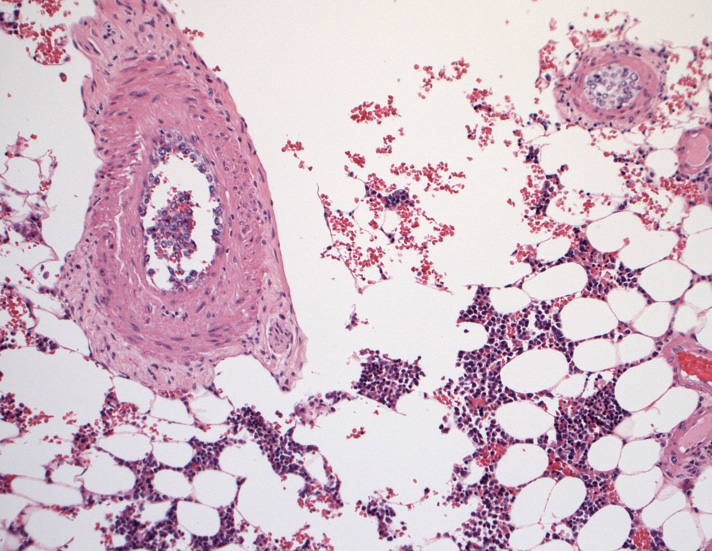

骨髄;細動脈内のみに腫瘍細胞が認められた。類洞や髄内での増殖は見られなかった。

(骨髄穿刺吸引では発見できなかった原因のようです。骨髄生検で細動脈がとれないと診断に結びつかなかったでしょう。)

骨髄の組織所見

肺組織所見